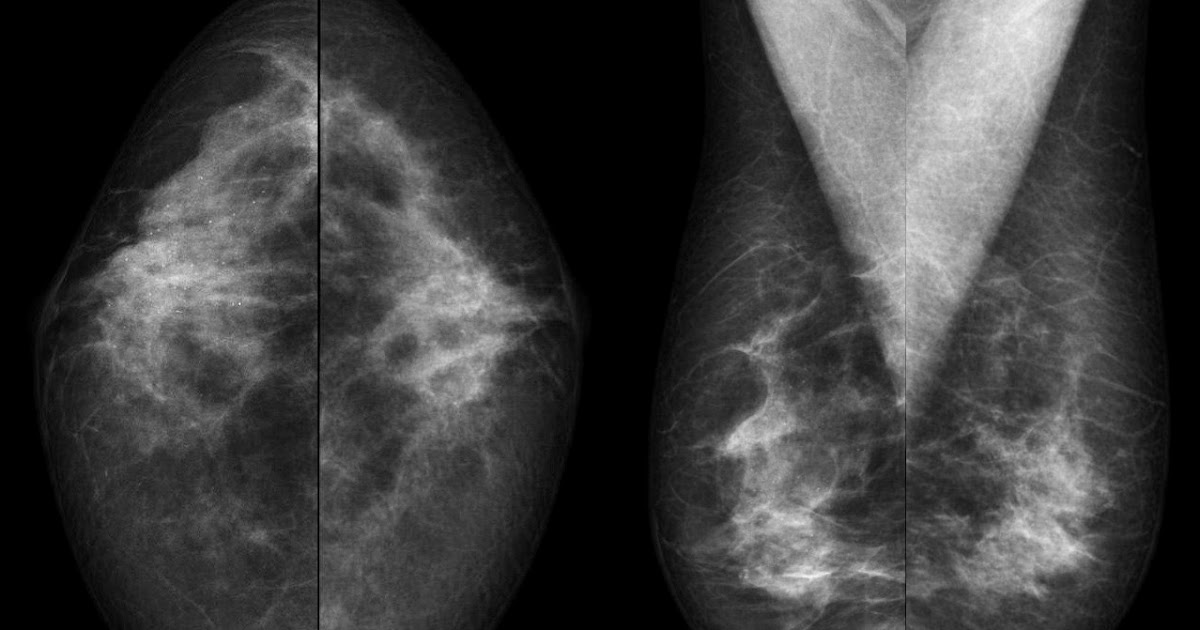

Sistema BI-RADS ¿Cómo se interpreta una mamografía? - Ondas y Partículas

WebEn la mamografía un BIRADS 2 significa que el estudio es normal pero que presenta hallazgos benignos a mencionar como por ejemplo calcificaciones de la piel,. WebPara el diagnóstico se usó la escala de Breast Imaging Reporting and Data System, BIRADS, edición 5 13, con el fin de agrupar los hallazgos de la mamografía, ecografía y. Web2 Hallazgo benigno (no canceroso) También se trata de un resultado negativo del mamograma (no hay signos de cáncer), pero el radiólogo decidió describir algún.